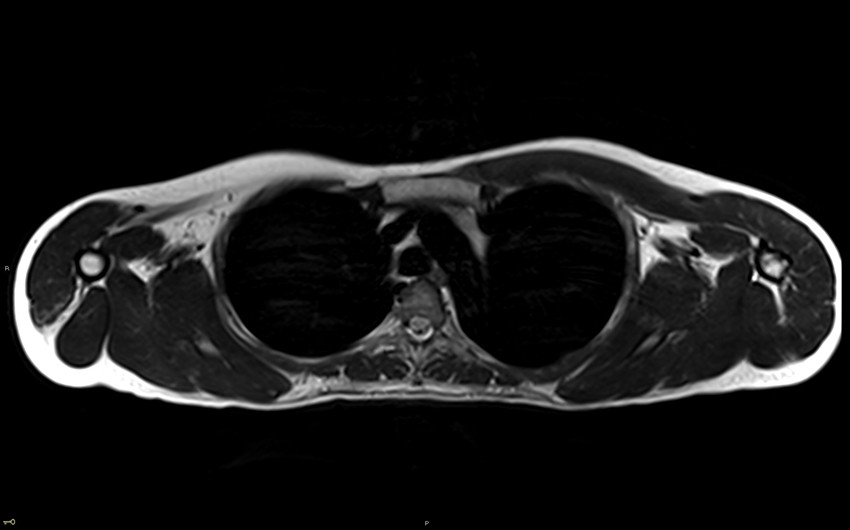

MR-bildet viser et snitt av øvre thorax hos en pasient i 20-årene med påvist facioscapulohumeral muskeldystrofi (ofte forkortet FSHD) type 1. Bildet viser uttalt atrofi av musculus (m.) trapezius bilateralt, uttalt atrofi av m. pectoralis major og minor på høyre side og lett atrofi av m. pectoralis major og minor på venstre side. Videre ser man uttalt atrofi av m. serratus anterior bilateralt, m. deltoideus på høyre side og m. rhomboidei på venstre side. Det ble også påvist ødem og kontrastoppladning i venstre m. serratus anterior og nedad i venstre m. pectoralis major.

MR brukes i økende grad for identifikasjon av affiserte muskler hos pasienter med muskeldystrofi. En MR-studie har vist et spesifikt mønster av muskelaffeksjon hos ca. 80 % av FSHD pasienter. MR kan også bidra til å skille FSHD fra andre muskeldystrofier (3).